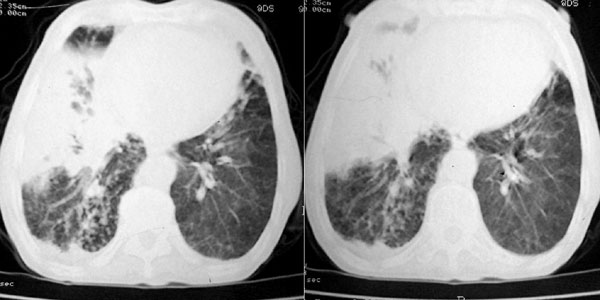

f 76 间断咳嗽 咳痰1年余 发热不明显 身体削瘦

征象:

1、右肺中叶近肺门区可见一空洞样病灶,内壁不规则,有与邻近支气管相通的征象,其外侧大片肺组织软组织状实变,余肺可见散在点、片絮状密度增高影,肺纹理可见明显增粗及串珠样改变;

2、纵隔气管前、隆突下、内乳组、心右前间隙以及右侧腋窝内均可见肿大的淋巴结节;

3、右侧胸膜增厚粘连,胸腔少量积液征像;

4、其它征像略。

诊断意见:

1、右侧中央型(空洞性)肺癌并双肺受累(包括转移、阻塞性炎症、癌性淋巴管炎);纵隔、右侧腋窝内淋巴结肿大、转移;右侧胸膜增厚粘连,胸腔少量积液;

2、双上肺陈旧性结核。

3、慢性支气管炎、肺气肿。